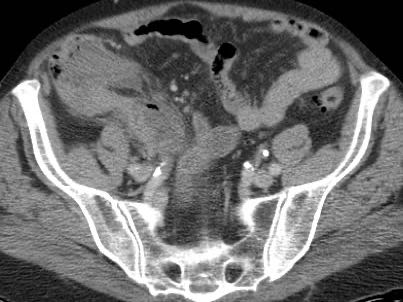

Ở bệnh nhân này với đau hố chậu phải kéo dài 18 giờ, CT chỉ cho thấy hình ảnh thâm nhiễm mỡ tối thiểu xung quanh ruột thừa 8,5 mm (mũi tên).

Siêu âm với kỹ thuật ép có kiểm soát đã cho thấy rõ ràng mô mỡ viêm tăng âm, không thể ép xẹp (đầu mũi tên) xung quanh ruột thừa.